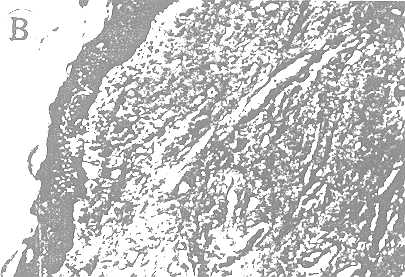

Figure B

Figure B: Inner layer of prepuce. Note absence of any glandular structure.

Histology. Histologic findings are summarized in table 3. Detailed examinations were performed on 128 specimens. Multiple small pieces were taken from the inner lining of the circumcised prepuce and also from the glans lining in cadavers. The pieces were serially sectioned and every fifth section was studied using hematoxylin and eosin stain. A special search was made for glandular tissue. No such tissue was found in the material (part B of figure). Chronic inflamatory changes and scarring were noted in most of the material from adults.